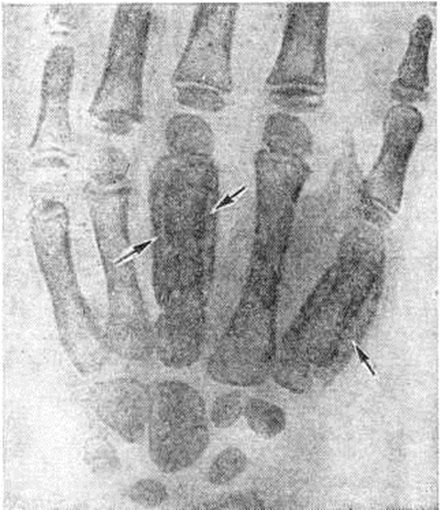

Медицинские аспекты заболеваний: рентгенологическая картина туберкулеза костей

Раздел: Снимки-откровения